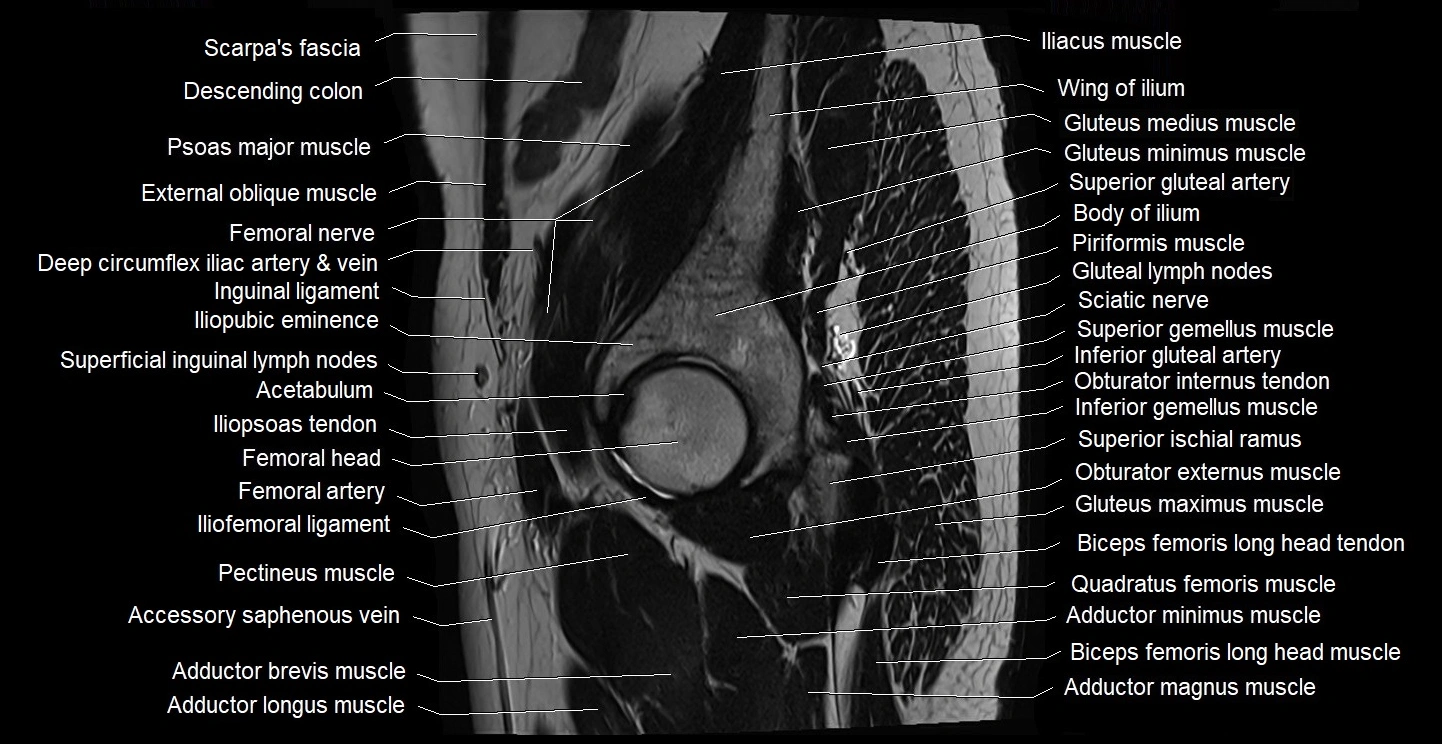

- Acetabulum

- Adductor brevis muscle

- Adductor longus muscle

- Adductor magnus muscle

- Adductor minimus muscle

- Femoral nerve

- Femoral artery

- Gluteal lymph nodes

- Gluteus maximus muscle

- Gluteus medius muscle

- Gluteus minimus muscle

- Iliofemoral ligament

- Iliopsoas tendon

- Iliopubic eminence

- Inferior gemellus muscle

- Inferior gluteal artery

- Obturator externus muscle

- Obturator internus tendon

- Pectineus muscle

- Piriformis muscle

- Quadratus femoris muscle

- Sciatic nerve

- Superficial inguinal lymph nodes

- Superior gemellus muscle

- Superior gluteal artery